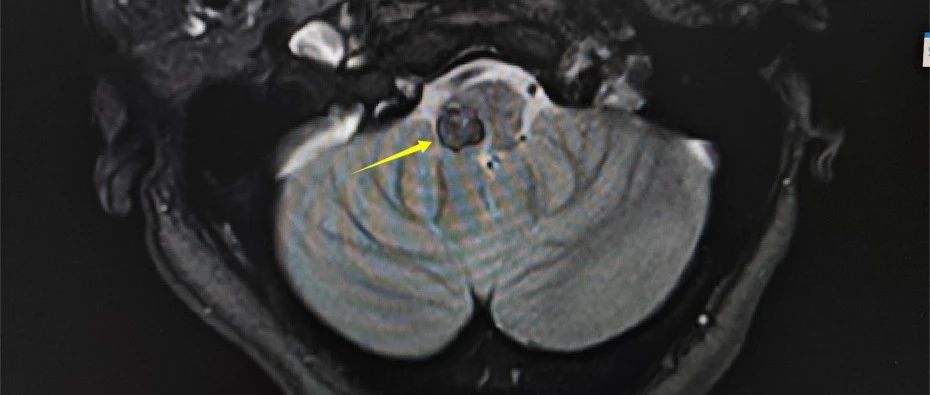

術(shù)前影像

患者李阿姨,54歲,因“右側(cè)肢體無力”入院。她在當(dāng)?shù)蒯t(yī)院做了顱腦CT,提示腦干出血,經(jīng)相關(guān)藥物治療,未見明顯效果。在朋友介紹下,李阿姨找到了惠州三院神經(jīng)外科負責(zé)人景英朝主任醫(yī)師。結(jié)合病史和查體,進一步完善顱腦磁共振等檢查,醫(yī)生發(fā)現(xiàn)腦橋左側(cè)有一類圓形占位,信號不均勻,考慮腦干海綿狀血管瘤可能性大,需要住院治療并完善檢查!

景英朝主任醫(yī)師介紹,海綿狀血管瘤是由眾多薄壁血管組成的海綿狀異常血管團,并非真性腫瘤。海綿狀血管瘤有反復(fù)多次出血的特點。由于腦干內(nèi)存在重要的神經(jīng)傳導(dǎo)束和眾多神經(jīng)核團,腦干海綿狀血管瘤出血可引起嚴(yán)重的神經(jīng)功能障礙,給患者帶來災(zāi)難性后果。經(jīng)學(xué)科討論,患者手術(shù)指征明確,需手術(shù)切除海綿狀血管瘤,以減少出血導(dǎo)致嚴(yán)重神經(jīng)功能障礙的風(fēng)險。

考慮腫物位于延髓左側(cè)份,治療團隊決定采取后正中入路手術(shù),術(shù)中還使用了神經(jīng)電生理監(jiān)測、顯微鏡等高端手術(shù)設(shè)備加持,最大限度地保障手術(shù)安全。